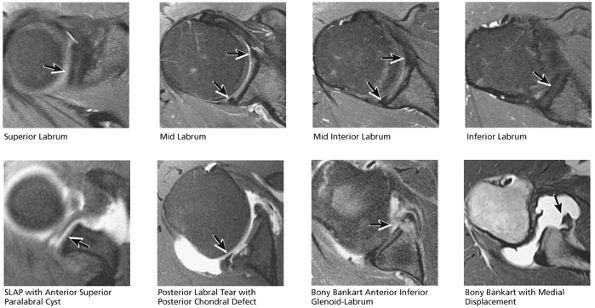

A separate FS PD-weighted FSE sequence is used to increase sensitivity to fluid and to identify paralabral cysts, articular cartilage labral avulsions, and muscle edema (Fig. 8.4). FSE sequences are less sensitive to intralabral signal intensity in the spectrum of degenerations or tears unless there is imbibed fluid. FSE (FS PD FSE) images, however, are superior for the demonstration of labral morphology in cases of avulsions or contour abnormalities.

without a FS PD FSE sequence to improve sensitivity for fluid and subtle labral tearing at the glenoid rim attachment.

FIGURE 8.3 ● Glenohumeral joint contrast on axial T2* GRE image. Axial GRE images optimize visualization of intralabral signal and subscapularis tendinosis. FS FSE images are more sensitive to fluid collections, paralabral cysts, and articular cartilage.

FIGURE 8.4 ● (A) Axial FS PD FSE image shows intact and congruous humeral head and glenoid articular cartilage surfaces (arrows), separate from the high-signal-intensity intra-articular contrast. (B) PD FSE contrast without FS is shown in an axial image of a Bankart lesion. Chondral surfaces are not as well demonstrated. (C) Excellent contrast is shown between the avulsed anterior labrum and the anterior glenoid rim on the corresponding sagittal FS PD FSE image.